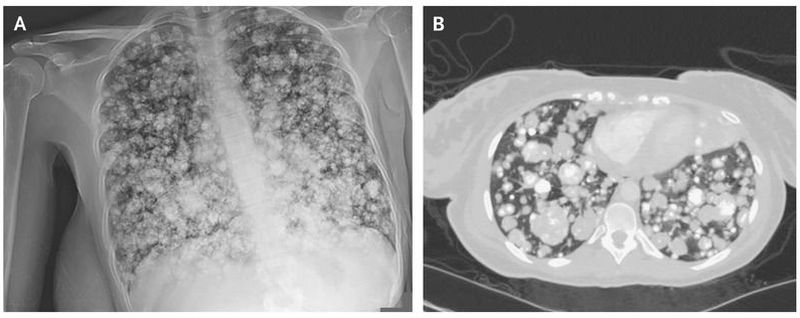

A 21-year-old woman presented to the emergency department with an 8-month history of progressive swelling and pain in the right thigh. Magnetic resonance imaging of the right leg revealed a large, enhancing, circumferential periosteal femoral mass that measured 30 cm in the craniocaudal dimension, as well as a nonocclusive thrombus in the right femoral vein, for which the patient received anticoagulation. Biopsy of the femoral mass confirmed a diagnosis of chondroblastic osteosarcoma. One week later, the patient had shortness of breath and left pleuritic chest pain. The oxygen saturation was 94% while the patient was breathing ambient air. Chest radiography revealed innumerable lesions in both lungs (Panel A). Computed tomography of the chest confirmed the presence of extensive, lobulated, and partially calcified nodules and masses throughout both lungs, a finding suggestive of pulmonary metastases (Panel B). Despite the initiation of chemotherapy, the disease progressed. A second chemotherapy regimen was started; five cycles have been completed, and the disease is currently stable.